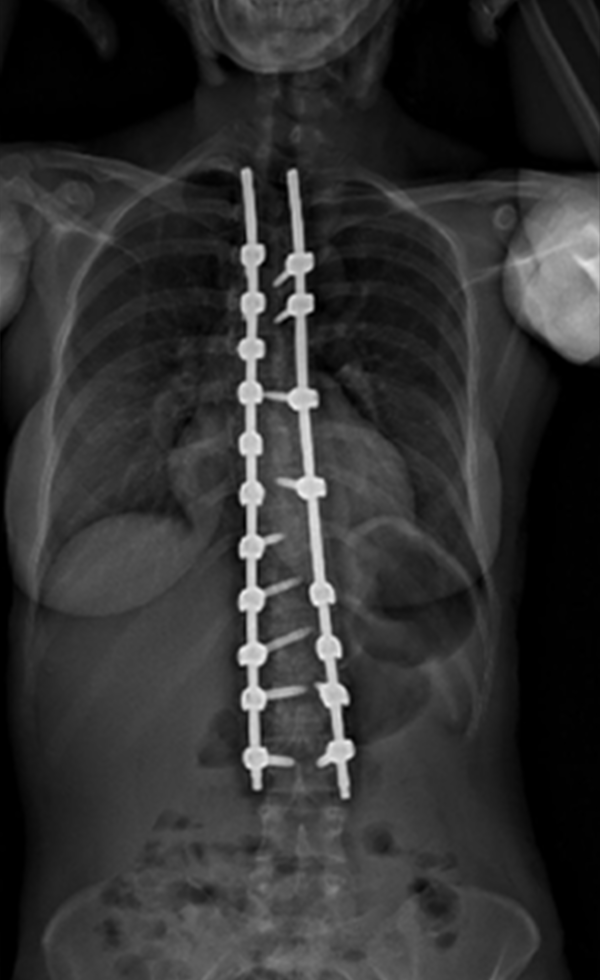

Gallery : Before - After